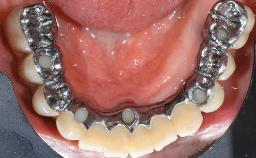

A 73-year-old woman was referred to the Division of Periodontology (University of Geneva School of Dental Medicine) after repeated unsuccessful treatment of a peri-implant infection. She was systemically healthy and did not smoke. The patient’s history revealed that, three years earlier, an immediate implant (Straumann Tapered Effect RN 4.8/4.1; Institut Straumann AG, Basel, Switzerland) had been inserted to replace the upper right central incisor. A metal-ceramic crown had been delivered using an adhesive resin cement. One year later, the patient had consulted another dentist due to discomfort in the soft tissues in the implant region. There was a suppurating peri-implant pocket, 10 mm deep. Peri-implant bone loss and excess luting cement were seen on the radiograph. The situation was treated with non-surgical debridement, amoxicillin, and repeated submucosal irrigation with a chlorhexidine digluconate solution. The patient was referred after the suppuration had persisted for several months.